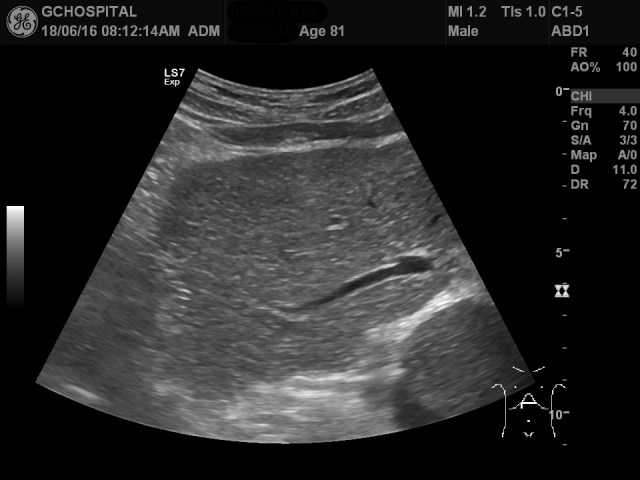

그런데, 췌장의 모양이 좀 이상합니다. 췌장의 머리와 몸통 모양이 잘 그려지지 않고, splenic vein 및 portal vein의 모양이 좌우가 뒤바뀌어 있습니다.

췌장의 위쪽에 있을 간 좌엽의 형태도 이상합니다. 간 좌엽에서 보여야 하는 좌측 간문맥이 정상적인 모양이 아닙니다.